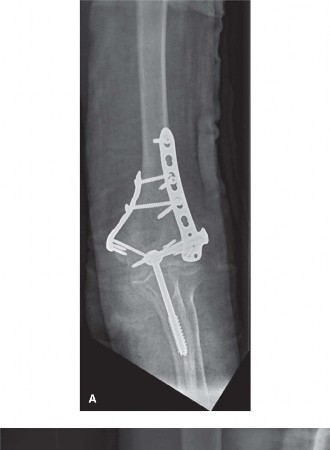

- Parallel Plating:

- Both plates are placed on the posterior aspect of the medial and lateral columns. This arrangement is often preferred for its ease of application, reduced hardware prominence laterally, and excellent biomechanical stability, particularly against torsional loads.

- Screws are directed to engage the opposite column or to maximize bone purchase within their respective columns.

- Caption: Parallel plating construct. Both plates are positioned on the posterior aspect of the medial and lateral columns, providing robust fixation.